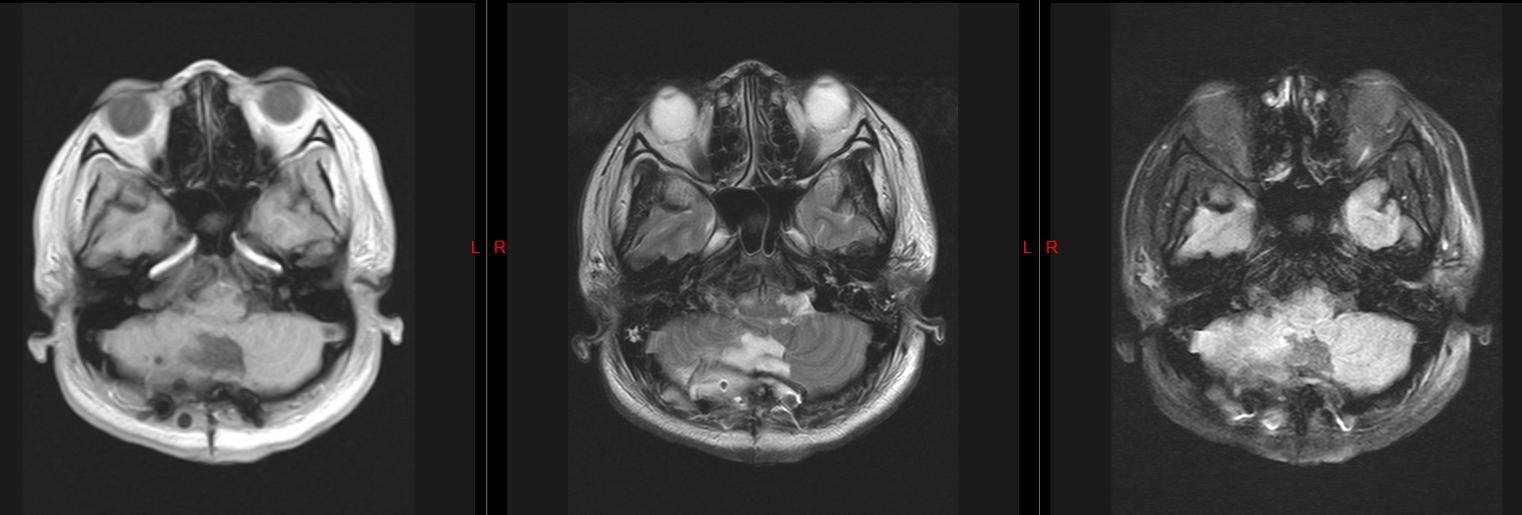

头颅磁共振检查结果显示

我的小脑上长了一个 肿瘤

压迫脑干

并且还有 脑积水

创伤外科二病区主任、主任医师张辉:结合目前症状和影像学检查显示,你的小脑肿瘤考虑皮样囊肿的可能性大,且合并梗阻性脑积水,需要进行手术治疗。

皮样囊肿是一种比较少见的颅内先天性良性肿瘤,属 先天性疾病 ,起源于异位的胚胎上皮细胞,是胚胎发育早期在神经沟封闭时将部分皮肤组织带入的结果。

皮样囊肿的基底层内含有较多的纤维组织及真皮层, 内含皮肤的附件如汗腺、皮脂腺及毛囊等 。

术后复查头颅磁共振

肿瘤完整切除